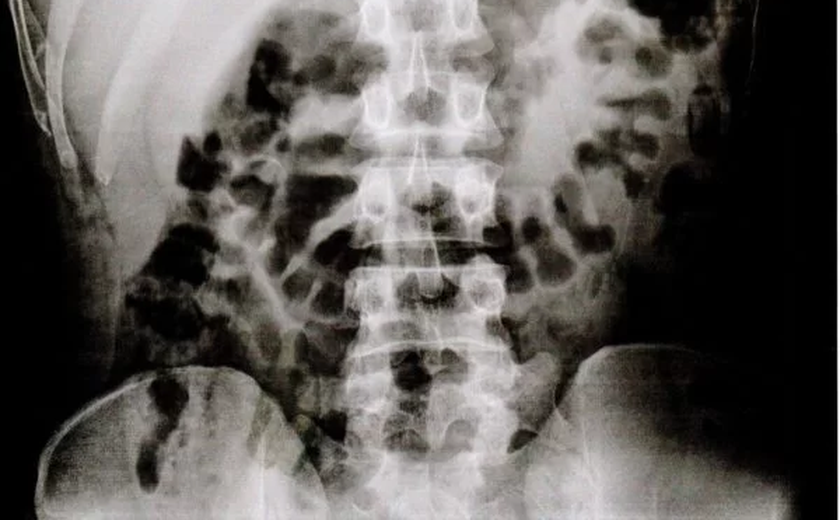

Somente no Centro de Progressão Penitenciária (CPP) II, em Bauru, foram registrados 19 casos do tipo. Em um deles, um reeducando teve de passar por uma endoscopia para a retirada de um minicelular do estômago.

De acordo com a SAP, o homem engoliu o aparelho para levar à unidade prisional após usufruir da “saidinha”. Ele chegou a ficar por quase uma semana na enfermaria, para tentar ejetar o celular de forma natural. Como não conseguiu, o homem foi encaminhando ao Hospital Estadual (HE), onde passou pela endoscopia.

O preso recebeu alta e passa bem. O aparelho foi apreendido.

Dos 19 casos registrados nesse CPP, 15 deles engoliram entorpecentes e aparelhos eletrônicos. Já em relação a todo estado, dos 101 detentos flagrados com ilícitos no estômago, sete tiveram de passar por algum procedimento médico para a retirada dos itens.